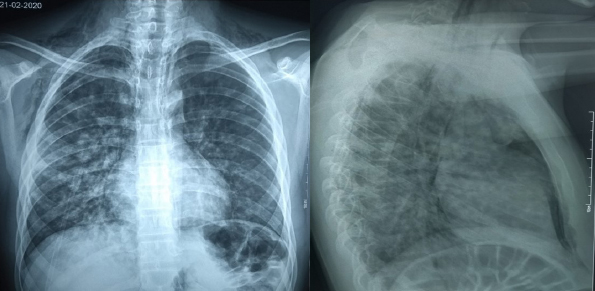

La radiografía de tórax posteroanterior y lateral muestra sombras lineales a ambos lados y a lo largo de los márgenes mediastínicos. Además, se visualizan ambos diafragmas sin interrupción en la línea media y presencia de aire retroesternal. También se observa en los tejidos blandos del cuello y tórax superior imágenes radiolúcidas irregulares que sugieren enfisema subcutáneo. No hay evidencia de fractura costal, neumotórax o derrame pleural concomitante (Figura 1).

Figura 1 Neumomediastino y Enfisema subcutáneo.